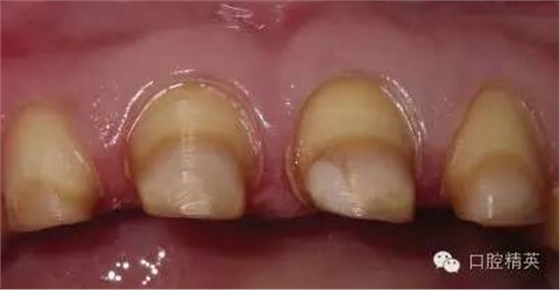

關(guān)于基礎(chǔ)治療。牙周治療和根管治療是美觀修復(fù)的基礎(chǔ)。根據(jù)術(shù)前檢查,常規(guī)先行全口潔治,必要時(shí)局部深層次的牙周治療,待牙周情況穩(wěn)定后,再考慮牙體預(yù)備與取模(見圖1、2)。在牙周炎未控制或牙齦紅腫的情況下,是不可能預(yù)備好牙齒,不可能取得清晰的印模,更談不上成功的美觀修復(fù)。

根管治療更是牙體修復(fù)的基礎(chǔ),根據(jù)術(shù)前診斷,對(duì)需要做根管治療的或有必要重新做根管治療的,一定要做到恰充,消除隱患,避免將來冠修復(fù)好后,出現(xiàn)根尖炎癥的問題(見圖3、4、5)。在基礎(chǔ)工作做好后,接下來開始牙體預(yù)備,根據(jù)跟個(gè)人習(xí)慣,選擇合適的車針(圖6、7)。

LAVA 全瓷冠強(qiáng)度高,顏色自然,邊緣高度密合,切端可見半透明感,整體效果理想,與修復(fù)前(見圖1)相比取得了醫(yī)患均滿意的效果。